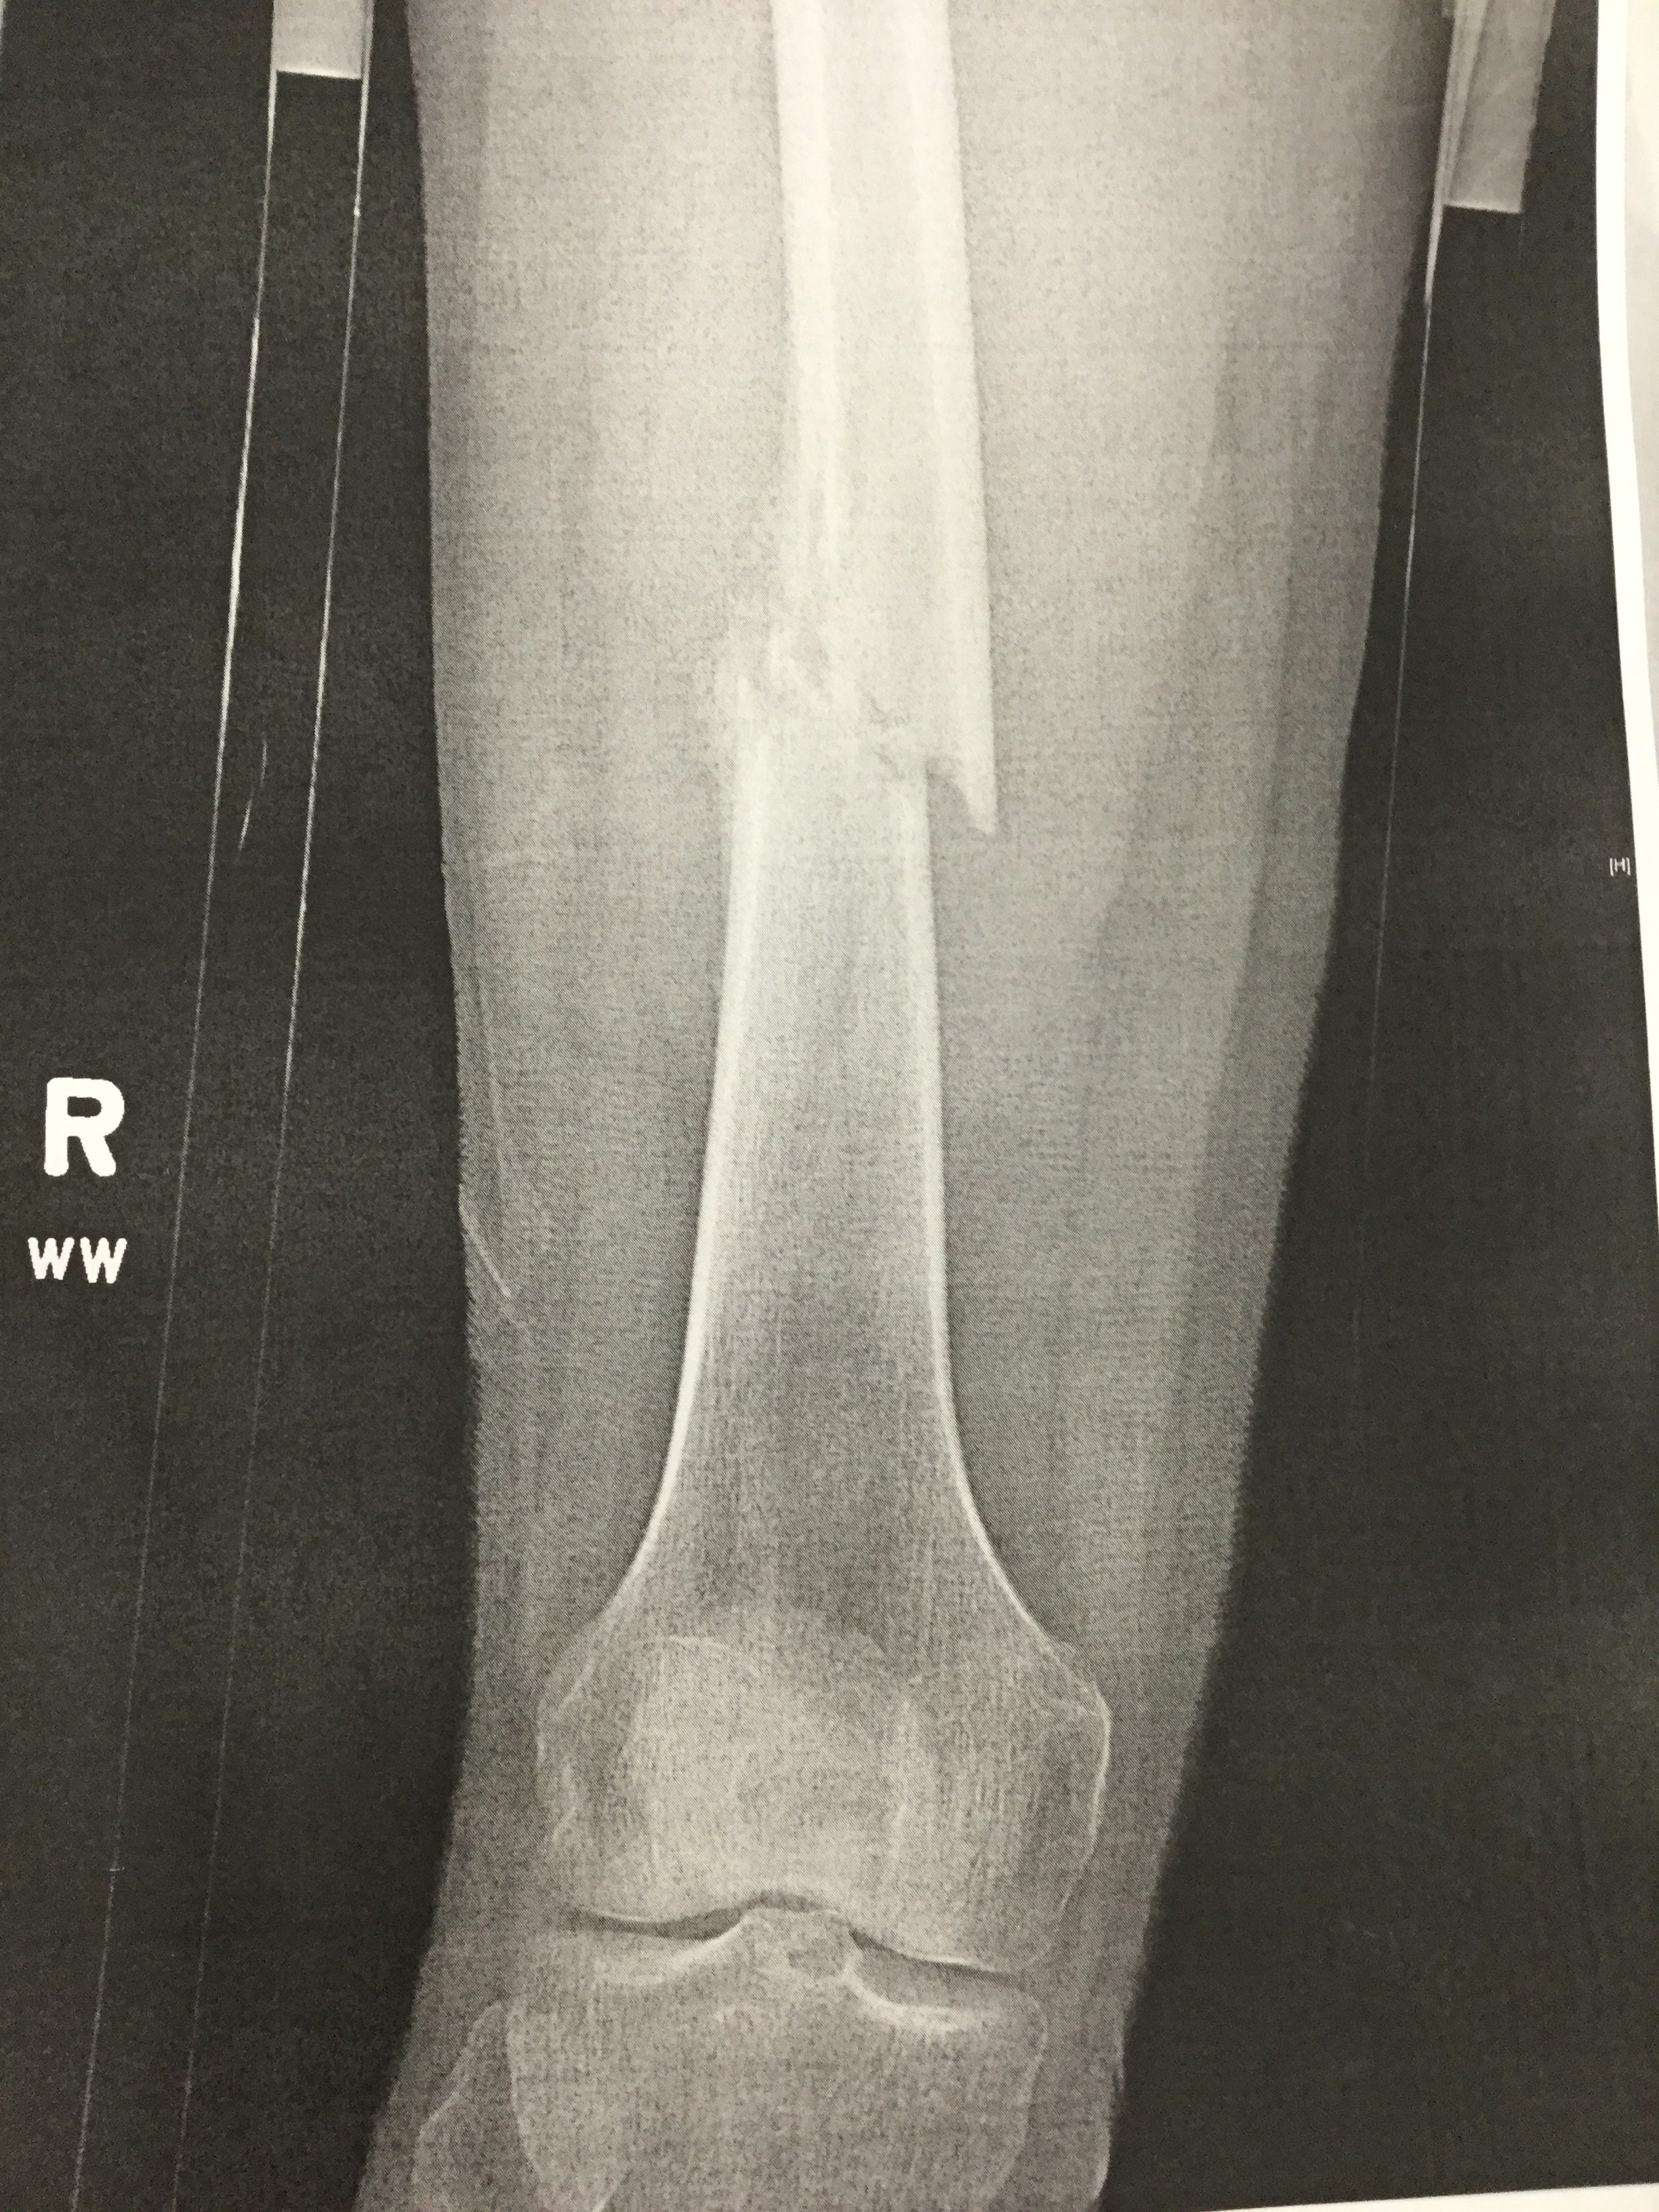

Contributors: Travis Barlock MD, Jeffrey Olson MS4 Feel free to use the cases below for your own practice. All of the scenarios are completely made up and designed to hit several teaching points. Case 1 25 M, presents to the ED with chest pain. Stabbing, started a few hours ago, substernal. Thinks it is GERD. After 2-3 minutes, pain worsens and radiates to the back. VS: BP 125/50 (Right arm 190/110). HR 120. RR of 18. Sat 98% on RA. Additional VS: Temp of 37.2, height of 6'5", BMI of 18. PMH: None, doesn't see a doctor. Meds: None FH: Weird heart thing (Mitral Valve Prolapse), weird lung thing (spontaneous pneumothorax), tall family members with long fingers and toes Physical Exam: Cards: Diastolic decrescendo at the RUSB, diminished S2. UE pulses are asymmetric, LE pulses are asymmetric, carotid pulses are asymmetric, BP is asymmetric MSK: Knees, elbows, and wrists are hypermobile. Imaging: CXR #1 normal, #2 widened mediastinum (no read yet but shows widened mediastinum), POCUS shows small effusion CTA/MRA doesn't come back until after the case. ECG: Sinus Tach Labs: NT-proBNP 500 pg/mL D-Dimer: 7000 ng/L CBC: Hemoglobin: 13.5 g/dL, WBC: 20,000/µL, Platelets: 250,000/µL Chem 7: Na 138, K, 5.7, Cl 102, Bicarb 17, BUN 45, Creatinine: 3.5 mg/dL, Glucose: 180 LFTs: Albumin 2.4, Total protein 5.5, ALP: 140, AST: 3500, ALT: 2800, TBili: 3.2, DirectBili: 2.4, Ca: 7.8 LDH: 2200 PT: 20.5, INR: 2.2, Fibrinogen: 170 5th gen High-Sensitivity Troponin: <3 Lactate: 7 mmol/L VBG: pH 7.22, paCO2 28, bicarb 15 Notes: Can have patient crash somewhere in middle and show 2nd xray Case 2: A 67-year-old female is brought to the ED by her daughter due to progressive weakness, confusion, and fatigue that have worsened over the past week. Unable to get out of bed and has become increasingly lethargic. Also having some nausea, constipation. The daughter denies any preceding illness, recent trauma, or travel. Does not know her meds but will head home to get them after talking with you. VS: BP 88/55 mmHg, HR 110, RR 20, O2 Sat 98% on room air. Additional VS: Temp 36.8°C. PMH: Hypertension, osteoarthritis, and depression. Physical exam: General: Thin, somnolent but arousable. HENT: Dry mucous membranes Neuro: Confused, A&Ox1 (self), hyporeflexia Labs (Includes many that would not return in the ED in case you want to take this case forward to the floor) CBC: WBC 9,500, Hb 16.5, Hct: 50%, Platelets 220,000 Chem7: Na 129, K 2.1, Cl 95, HCO3 34, Creatinine 1.6, BUN 40, Glucose 115 LFTs: normal Magnesium: 1.1 Calcium: 10.8 mg/dL (corrects to 12.8) iCal: 3.2 Phosphate: 2.3 mg/dL Albumin: 2 BUN:Cr ratio: 25 VBG: pH: 7.49, PaCO2 45, HCO3: 34 Lactate: 2.8 Serum Osmolality: 276 mOsm/kg (Osmolal gap of 2) Urine Osmolality: 550 mOsm/kg Urine Sodium (UNa): 10 mEq/L (low). Urine Potassium (UK): 25 mEq/L (elevated). Urine Chloride (UCl): 12 mEq/L (low). Urine Magnesium (UMg): 20 (Elevated). Urine Calcium (UCa): 50 in 24 hrs (Low) 100 cc of urine with foley FeNa Plasma renin activity: 15 mg/mL/hr (elevated), Aldosterone: 25 ng/dL (Elevated), ADH: Elevated, Diuretic screen: Positive for thiazides PTH: 8 (low), HsTrop: 32, Cortisol and ACTH: Normal. EKG: Hypokalemia features CXR: Normal Renal US: shows stones Improves with fluids Note: Can have daughter return with med list at some point including HCTZ, ibuprofen, and sertraline Case 3: Patient Presentation EMS Report: A 27-year-old male involved in a high-speed motorcycle collision is brought to the emergency department by EMS. The patient was found unconscious at the scene with evidence of severe thoracic and extremity trauma. He was intubated en route for airway protection due to altered mental status (GCS 7). VS: HR 130, BP 90/60, RR: bagging at 12 bpm, satting 88% on 100% FiO2 Primary Survey Airway: Endotracheal tube in place. Breathing: Decreased breath sounds on the left side with visible chest asymmetry and paradoxical chest wall movement. Circulation: Mottled extremities noted, with significant deformity of the right thigh. Pulses are diminished in the right leg Disability: GCS remains 7 (E1 V2 M4). Pupils equal and reactive. Exposure: Full-body examination reveals an open fracture of the right femur, multiple abrasions, and bruising over the chest wall. Vent alarms Peak Inspiratory Pressure (PIP) 40 cm H₂O (elevated) Plateau Pressure (Pplat) 35 cm H₂O (elevated) EtCO₂ (End-Tidal CO₂) 55 mmHg High-Pressure Alarm Triggering frequently Glucose 120 CBC: Hgb 8.9, Hct 27, WBC 14.2, platelets 220,000 VBG: pH 7.28, pCO2 33, bicarb 18, lactate 4.5 CXR with tension pneumothorax Patient improves after chest tube, pigtail catheter, or needle decompression. Ready to be transferred upstairs and O2 starts tanking again Vent alarms- second episode Peak Inspiratory Pressure (PIP) 35 cm H₂O (elevated) Plateau Pressure (Pplat) 30 cm H₂O (elevated) EtCO₂ (End-Tidal CO₂) 20 mmHg HR: 140, satting 84%, temp 38.5, ABG: pH 7.32, pCO₂ 30 mmHg, pO₂ 60 mmHg on 100% FiO₂, HCO₃⁻ 18 mmol/L (hypoxemia and metabolic acidosis). D-dimer: Elevated Thrombocytopenia: Platelets 90,000/µL. US shows blown right ventricle ECG shows new RBBB CT PE: Ground glass opacities, consolidation, centrilobular nodules, septal thickening, and fat-attenuating lesions. Note: Management is largely supportive care so once the diagnosis is made, end the case. References Carroll MF, Schade DS. A practical approach to hypercalcemia. Am Fam Physician. 2003 May 1;67(9):1959-66. PMID: 12751658. Coelho SG, Almeida AG. Marfan syndrome revisited: From genetics to the clinic. Rev Port Cardiol (Engl Ed). 2020 Apr;39(4):215-226. English, Portuguese. doi: 10.1016/j.repc.2019.09.008. Epub 2020 May 18. PMID: 32439107. Palmer BF. Metabolic complications associated with use of diuretics. Semin Nephrol. 2011 Nov;31(6):542-52. doi: 10.1016/j.semnephrol.2011.09.009. PMID: 22099511. Reed MJ. Diagnosis and management of acute aortic dissection in the emergency department. Br J Hosp Med (Lond). 2024 Apr 30;85(4):1-9. doi: 10.12968/hmed.2023.0366. PMID: 38708978. Roberts DJ, Leigh-Smith S, Faris PD, Blackmore C, Ball CG, Robertson HL, Dixon E, James MT, Kirkpatrick AW, Kortbeek JB, Stelfox HT. Clinical Presentation of Patients With Tension Pneumothorax: A Systematic Review. Ann Surg. 2015 Jun;261(6):1068-78. doi: 10.1097/SLA.0000000000001073. PMID: 25563887. Rothberg DL, Makarewich CA. Fat Embolism and Fat Embolism Syndrome. J Am Acad Orthop Surg. 2019 Apr 15;27(8):e346-e355. doi: 10.5435/JAAOS-D-17-00571. PMID: 30958807. Produced by Jeffrey Olson, MS4 Special thanks to Evan Fisch MD Get your tickets to Tox Talks Event, Sept 11, 2025: https://emergencymedicalminute.org/events-2/ Donate: https://emergencymedicalminute.org/donate/